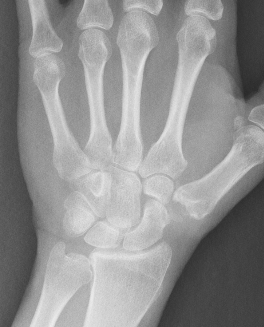

OA of the scapho-trapezium-trapezoidal (STT) joints

Third most common wrist osteoarthritis after CMC OA and SLAC wrist

- associated with CMC OA in 60% of cases

- often bilateral